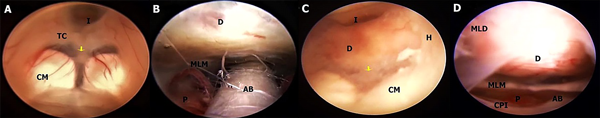

En este estudio fueron halladas 10 variedades anatómicas del piso anterior del tercer ventrículo, las cuales son en orden de frecuencia: piso opaco o grueso 54,90% (Figura 1), piso parcialmente borrado 29,41% (Figura 2), intervalo prepontino pequeño 23,53% (Figura 3), piso estrecho 17,65% (Figura 4 A-B), piso herniado 17,65% (Figura 5), piso delgado 11,76% (Figura 6), basilar elevando el piso 1,96% (Figura 4C-D), adherencias interhipotalámicas 3,92% (Figura 7), fenestración espontánea 1,96% (Figura 8), y piso sin reparos anatómicos 1,96% (Figura 9). Las primeras 7 según la descripción de Sughrue, a la cual se sustituye banda premamilar por adherencias interhipotalámicas, descriptas por Phillips4, fenestración espontánea al hallarse ausencia de PTV u ostomía espontánea como en la Fig. 8, reportada por Parmar5, y se introduce otra categoría no reportada, piso sin reparos anatómicos cuando no se pueden diferenciar los cuerpos mamilares ni el receso infundibular. En la mayoría de los casos se detectaron 2 o más variedades.

Figura 3: A-B Masculino con hidrocefalia crónica del adulto, de 76 años. Piso parcialmente borrado con intervalo prepontino reducido indicado en A con flecha amarilla, donde se ve una gran proximidad del dorso selar con los CM, reduciéndose la distancia entre el D y la AB, obligando a realizar una fenestración más lateral. Cuerpos mamilares de tipo Split. En B se observa el contenido de la cisterna interpeduncular del mismo caso tras la TVE, con la AB muy cerca del dorso selar. C-D otro ejemplo de IPR, pero con un piso opaco debido a ependimitis en un paciente con meningitis. Cuerpos mamilares de tipo kissing. AB arteria basilar; CM cuerpo mamilar; CPI arteria cerebral posterior izquierda; D dorso selar; H hipotálamo; I Receso infundibular; MLD membrana de Liliequist, hoja diencefálica; MLM hoja mesencefálica; P puente TC Tuber cinereum.

Figura 4: A-B En ambos casos se evidencia un piso de tipo opaco y estrecho, con un diámetro anteroposterior del tercer ventrículo significativamente mayor al diámetro transversal, con CM de configuración kissing. Los 2 casos corresponden a hidrocefalia aguda por hemorragia intraventricular, en A por ruptura aneurismática y en B por sangrado de tumor ventricular. C; TC de cerebro sagital de masculino con hemorragia intraventricular primaria, donde se observa tercer ventrículo repleto de sangre y arteria basilar alta, elevando el PTV, indicado con flecha amarilla, lo cual se constata en la imagen endoscópica en D, con un piso grueso y CM adyacentes. CM cuerpo mamilar; H hipotálamo; I Receso infundibular; TC Tuber cinereum